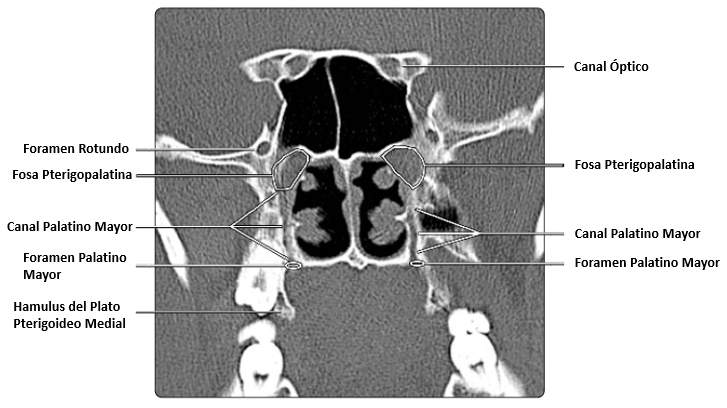

Imagen de tomografía axial computarizada vista desde una vista coronal. El nervio palatino mayor usa el canal palatino mayor para acceder al paladar.